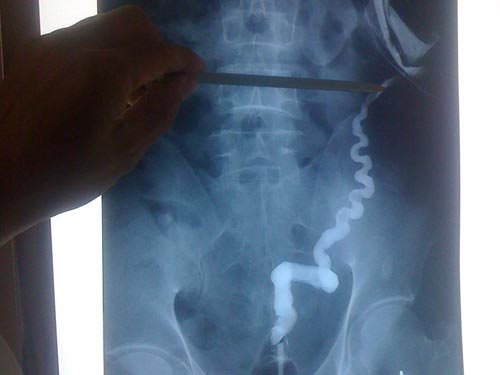

Đoạn ruột được đổ nước ấm nong ra và chỗ tiếp giáp giữa hai đoạn ruột của anh H. không đồng đều

Sau lần phẫu thuật lần đầu hạ niêm mạc trực tràng, tập nhu động ruột, nong ống hậu môn, tạo hậu môn mới, anh H. còn được hướng dẫn bơm nước ấm vào mỗi ngày sau xuất viện để nong đường ruột phía dưới bị teo sau hàng chục năm bỏ trống.

Ngày 10-10, anh trở lại bệnh viện để các bác sĩ tiếp tục công đoạn lần thứ 2 là nối ruột, thông ruột hoàn chỉnh, đóng lại lỗ hông trả chức năng như người bình thường.

Theo TS Đương, đây là ca phẫu thuật khó vì trực tràng, đại tràng teo lại, chỗ nối hai đầu ruột không đồng đều dễ bị bục ra nếu không xử lý chuẩn xác kỹ thuật, không có nhu động ruột, đường kính quá nhỏ.